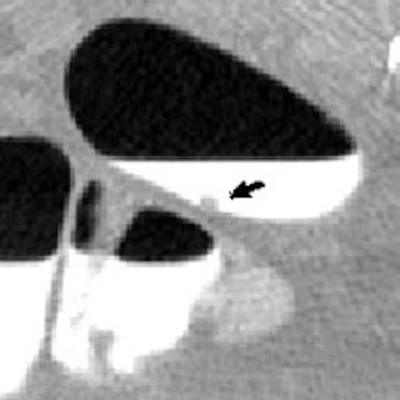

![]() |

| Above and below: Images from a second clinical case demonstrate adaptive correction with CAD. Top, lesion (arrow) covered by tagged fluid, seen with lung display window. Below, soft-tissue display window shows distortion of the polyp. Third from top, CT-value correction reduces polyp distortion. Bottom, CAD detection overlaid on lung display window. |